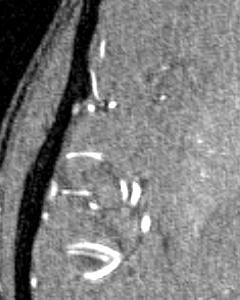

(a)

(b)

(c)

We perform three experiments to evaluate our method. (1) We compare the performance of our approach with commonly used unsupervised methods for vessel segmentation: Frangi [7], Sato [20], Hybrid Hessian [14] and Meijering [13] filters on four 2D datasets and two 3D datasets, all of which are publicly available. (2) We study the efficiency of learned representation for the downstream vessel segmentation task. To do that, we compare our method with existing self-supervised methods. (3) We examine the efficacy of the bifurcation loss in segmenting the regions around bifurcation points in 2D compared to methods which do not consider bifurcations.

Since our method is learning based, it can learn feature representations that are essential for vessel detection. This section compares the efficacy of the representation from different self-supervised tasks onto a downstream supervised vessel segmentation task. We compare our model with four self-supervision baselines, namely, context-encoder [17], image-denoising [24], image-colorization [26] and Models Genesis [27]. First, we train multiple networks using different pretext tasks on the DRIVE dataset. These networks are then finetuned on a supervised vessel segmentation task on the STARE dataset. We consider a limited-data and a high-data scenario, where finetuning is done with only 4 and 16 images respectively. Figure 2(a,b) show the training dynamics in both cases. Our method takes fewer iterations to converge compared to the other methods and achieves the best validation dice score.

3.3 Segmentation around Bifurcation Points (BPs)

(d)

(e)

In this experiment, we demonstrate the importance of our predicted bifurcation flow fields () in vessel-segmentation performance around BPs. To quantitatively measure the segmentation, we manually annotated bounding boxes (BBs) at multiple bifurcation regions in the DRIVE dataset. We performed an ablation study, where we didn’t consider bifurcation loss (BL) in our final formulation. Figure 2(c) reports the accuracy of identifying vessel pixels within the extracted BBs. Our proposed bifurcation loss significantly improves the segmentation at regions around BPs.